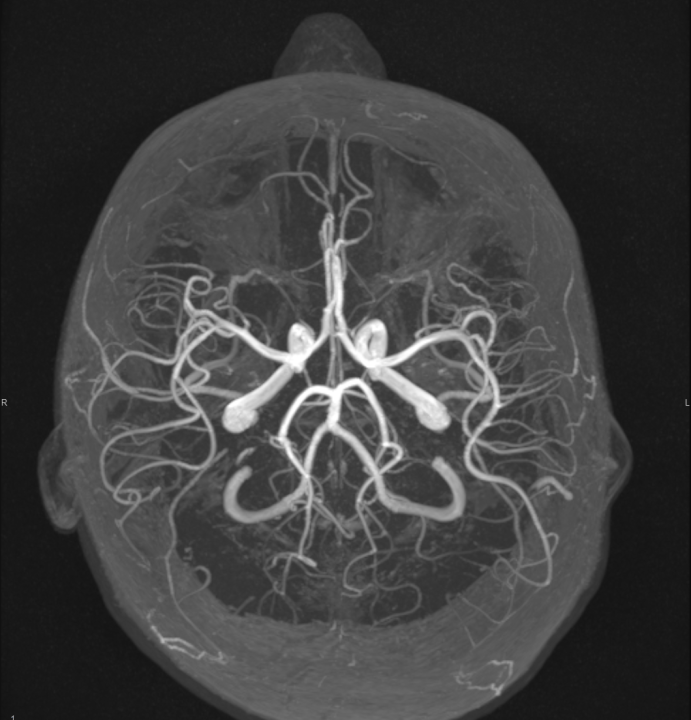

Tijekom Tjedna mozga Poliklinika Affidea Vita daje 20 posto popusta na magnetsku rezonancu!